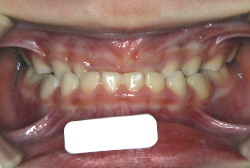

下顎前突・反対咬合

反対咬合とは、歯の生えてくる角度が悪くて下の前歯が上の前歯の外側に出てしまう”歯性反対咬合”と、上下の顎の骨の大きさと形に問題があることで起きる”骨格性反対咬合”に大別されます。骨格的な問題がないか、あったとしても軽度な場合は、大人でも矯正治療で改善することが出来ます。矯正治療のみで治せるのか外科矯正を併用した方が良いのかは、検査診断後に矯正専門医とよく相談して決めていただきます。

初診時の状態ですが、前歯の噛み合わせが逆転していて、下の前歯が外側に来て、上の前歯が裏側になっています。口元の様子ですが、前歯の重なり方が逆なので、唇の様子もそれを反映して、下唇が突出しています。反対咬合としてはかなり重症です。

分析してみると歯の傾き方に問題があるだけでなく、顎の骨の大きさと形にも問題があることが分かりました。ただし、骨の問題点が見つかったからと言って、必ずしも外科矯正になるわけではなく、このくらいの症状ですと、通常の矯正でもきれいに治すことができます。

診断の結果、下の前歯を正しい位置まで内側に入れていくためには、十分な隙間を確保することが避けられないと判断し、上の左右第二小臼歯と下の左右第一小臼歯は抜歯させて頂くことにしました。歯の本数は減りましたが、歯科医学的評価も大きく改善しましたし、審美的にも大幅な改善が見られますね。特に口元の様子が全然変わりました。